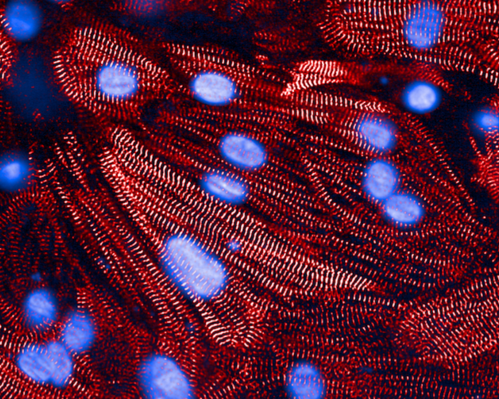

This groundbreaking form of personalized cancer immunotherapy has had remarkable success — more than 45,000 cancer patients worldwide have been treated with CAR T-cell therapy, extending their lives and, in many cases, delivering complete and sustained remissions.